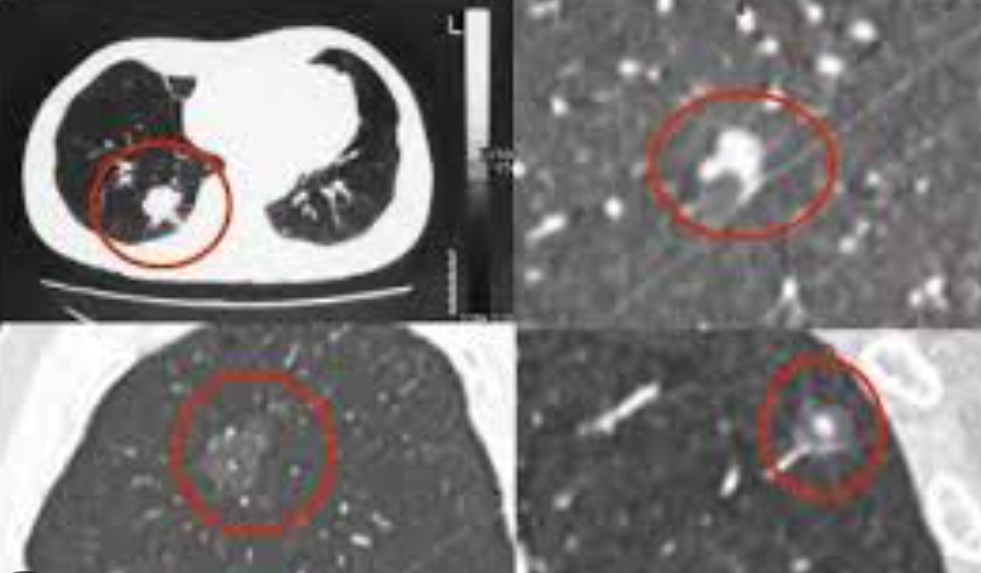

简单来讲,肺结节是指肺部影像学上

表现为 ≤ 3 厘米的高密度影。

一.先看「性质」:到底是「实性」还是「亚实性」?

实性结节:简单来说就是影像上显示看起来实打实的、边缘非常清晰的结节

亚实性结节:分为纯磨玻璃结节和混杂磨玻璃结节

磨玻璃是指从影像结果上,看起来比较朦胧,观察结节边缘有晕开的感觉。为什么要更警惕呢?